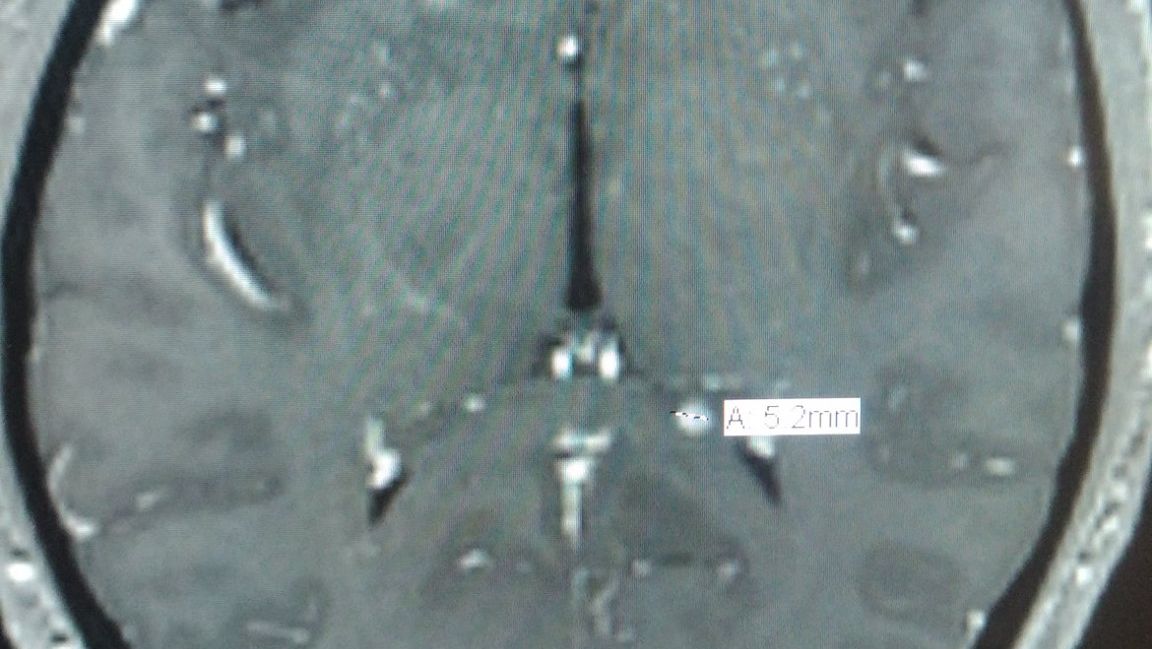

About 2 months ago, I was diagnosed with Brain Cancer. A 5.22mm Tumor in the left side of my brain. Not bad for a christmas present right?

I’m currently exploring options for treatment, obtaining an official biopsy if possible and looking into surgery for removing it. I dont know if its benign or not, but thats what I want to find out.